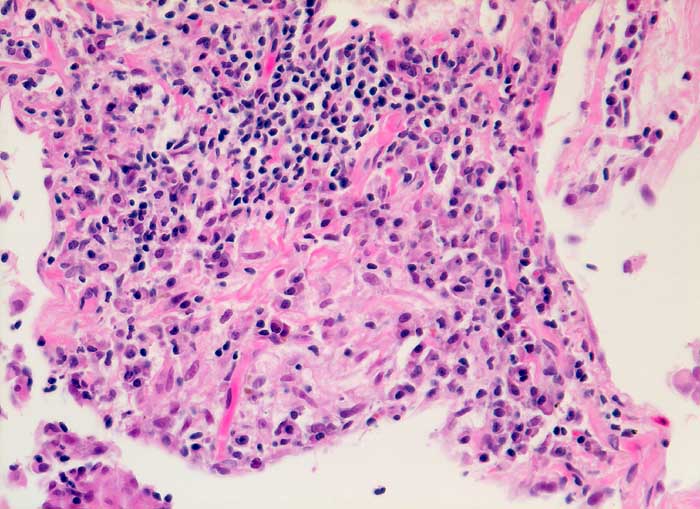

Die exogene allergische Alveolitis (Hypersensitivitätspneumonie) ist eine Entzündungsreaktion der Lunge, die bei prädisponierten Individuen durch pflanzliche oder tierische Inhalationsantigene ausgelöst werden kann. Die BAL Befunde hängen vom Stadium der Erkrankung ab. In der perakuten Phase überwiegen neutrophile Granulozyten. Ausserdem sind in den ersten Tagen der Exposition die Mastzellen auf über 1% erhöht (mehr als 3/10 HPF), um nach 1 bis 3 Monaten wieder auf Normalwerte abzufallen. Bei aktiver EAA besteht oft eine extreme Lymphozytose von 60-70%. Bei chronischer Erkrankung sind Schaumzellen, einige eosinophile Granulozyten und als Ausdruck der Fibrose reichlich neutrophile Granulozyten nachzuweisen.

Eine Lymphozytose von mehr als 100x10^6/L in der BAL zusammmen mit einem erniedrigten HS Quotienten von unter 0.5 sind bei entsprechendem klinischen Verdacht vereinbar mit einer exogenen allergischen Alveolitis.